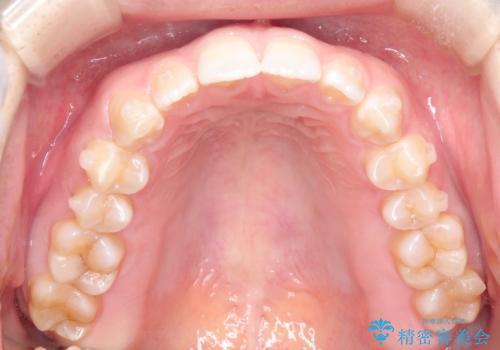

前歯の隙間を閉じたい インビザラインによる矯正

- 上下の前歯に隙間があるとのことで来院されました。

インビザラインにて隙間を閉じる矯正を行いました。

使用時間を守っていただけたので、比較的スムーズに矯正を終了することができました。